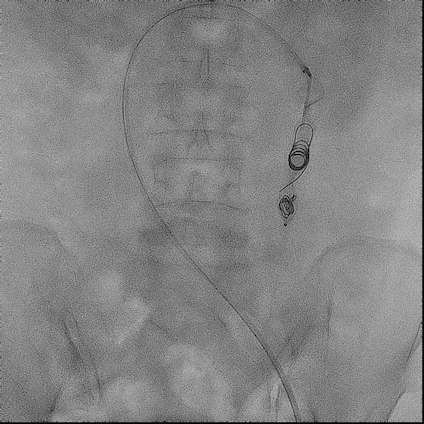

手术过程(五):

退导管至AVP Ⅱ网盘舱内,序贯植入Cook弹簧圈MWCE-35-14-14-NESTER、MWCE-35-14-20-NESTER、MWCE-35-14-14-NESTER,致密栓塞(coil in plug)。

图片图片图片